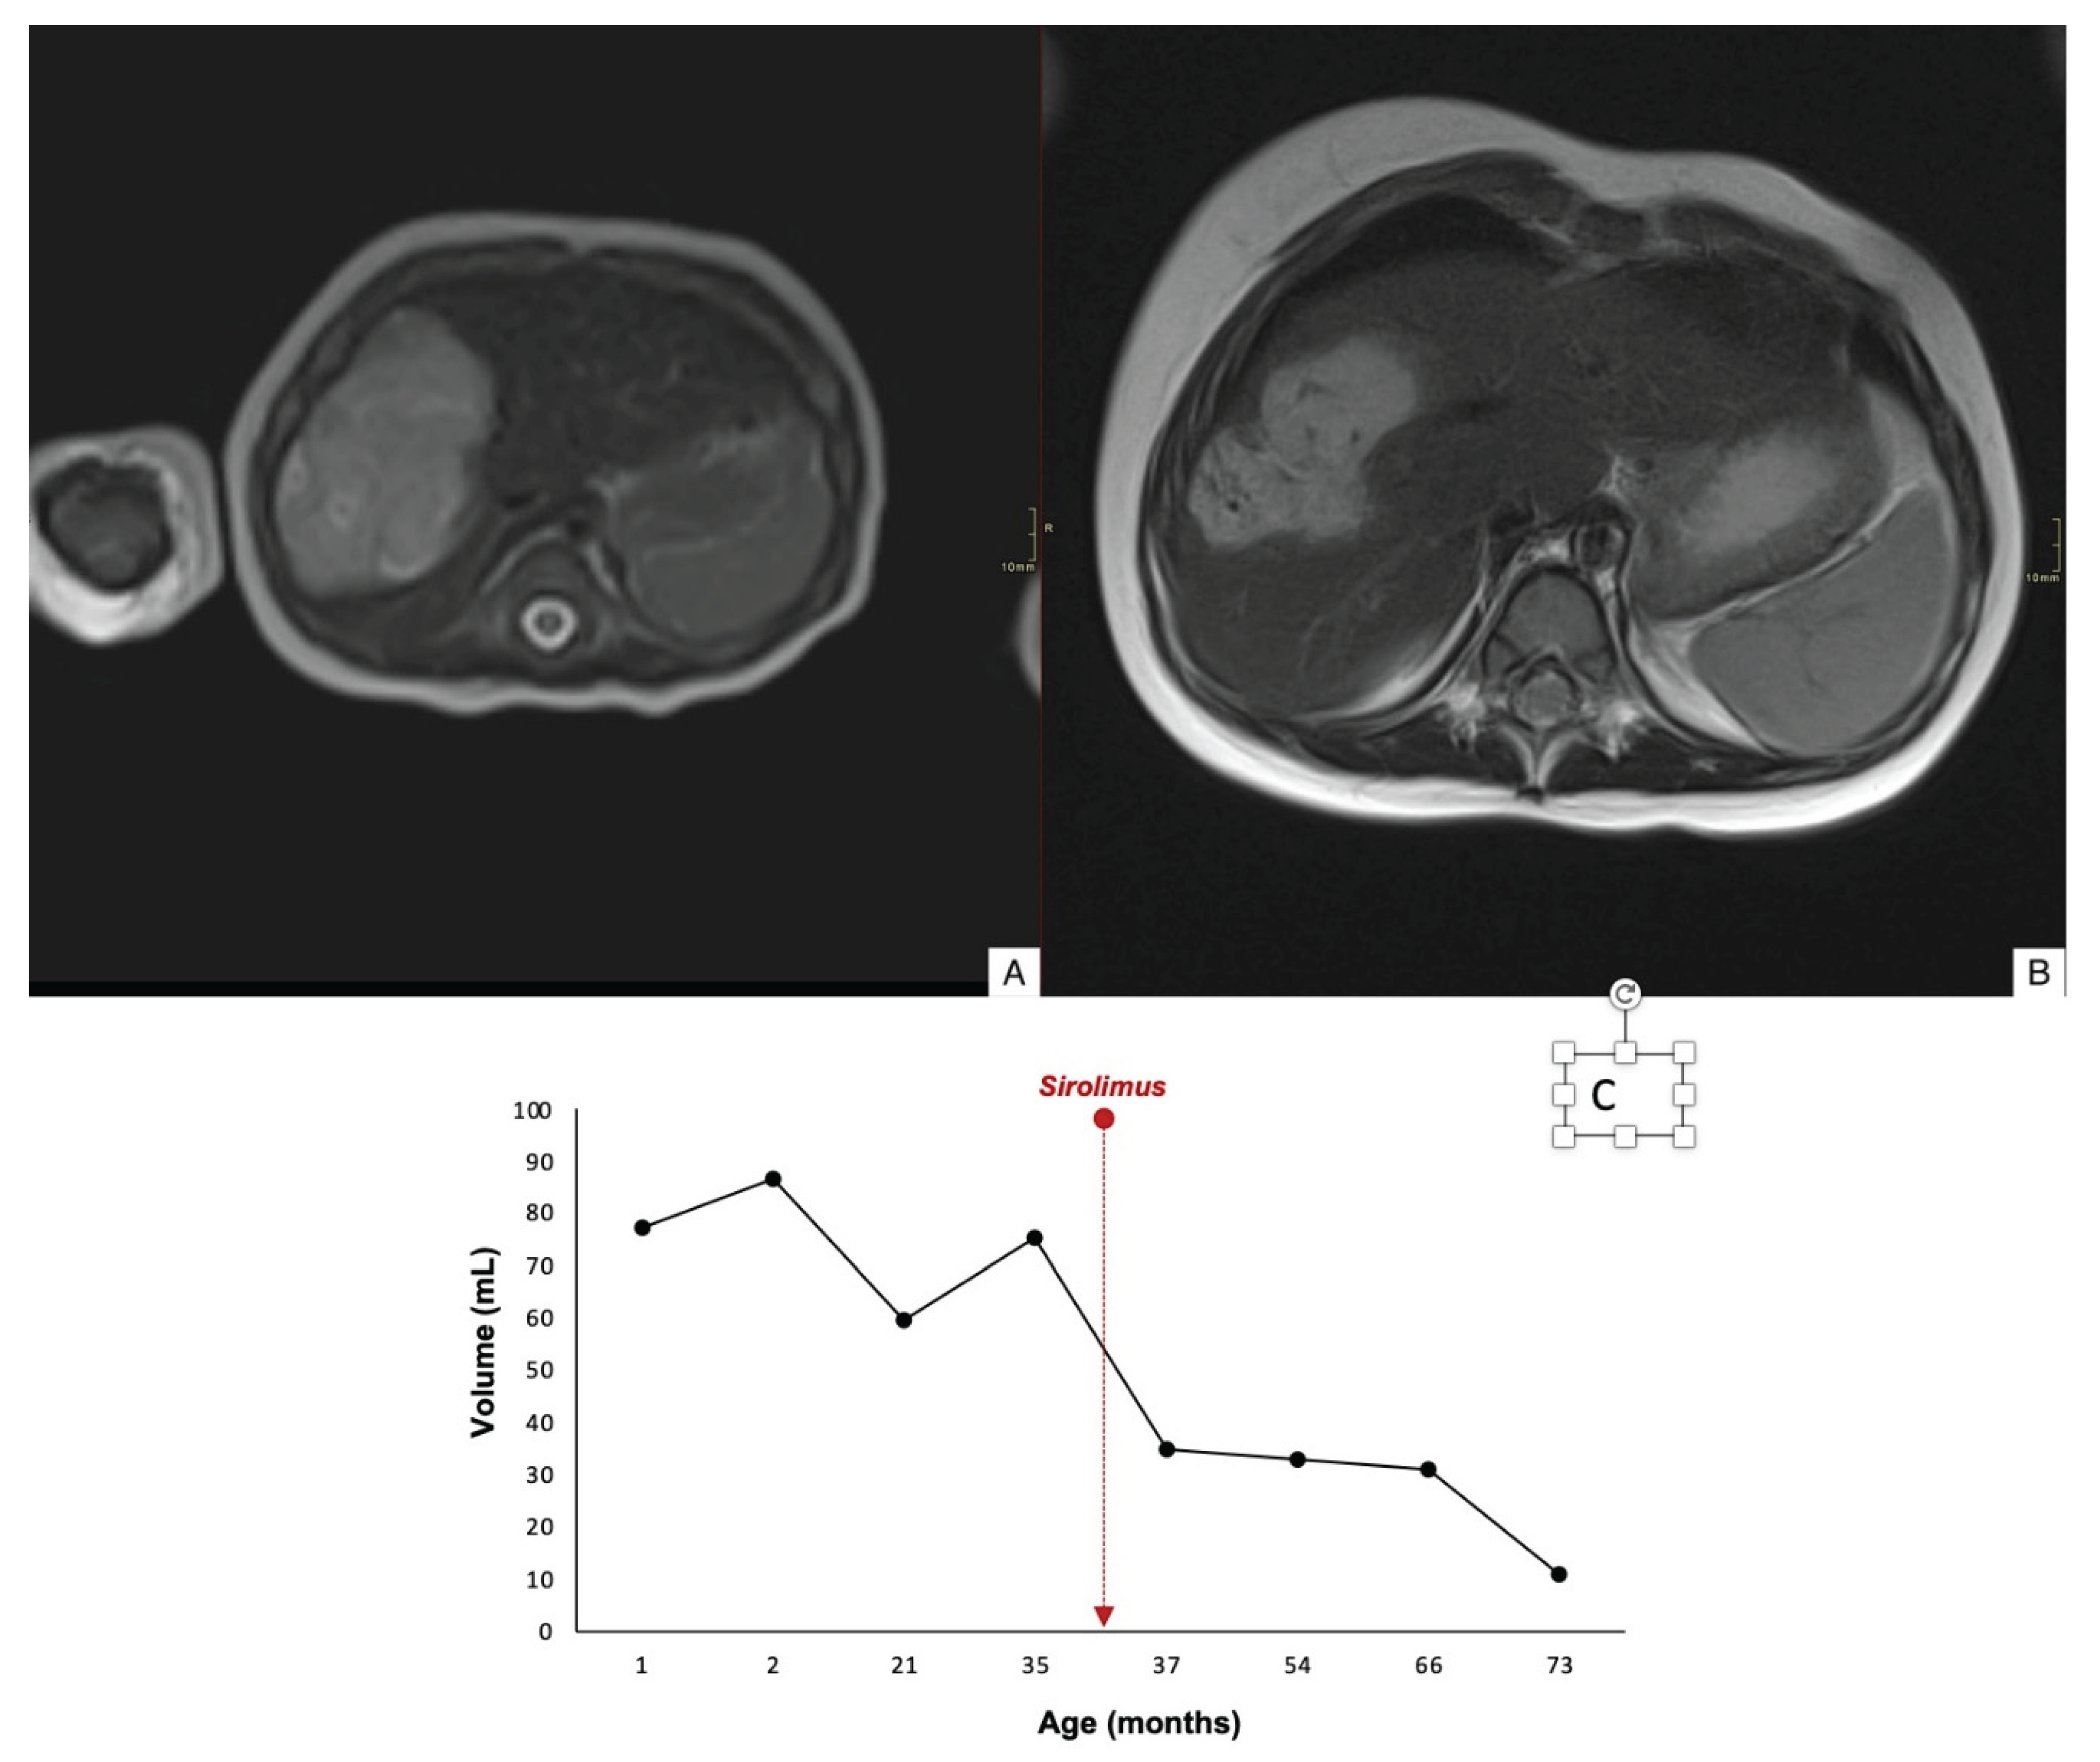

| 3 | 5 x 3.5 x 6 >4cm |

36 | Partial | 60 % | 34 | No | Yes | No | 81 |